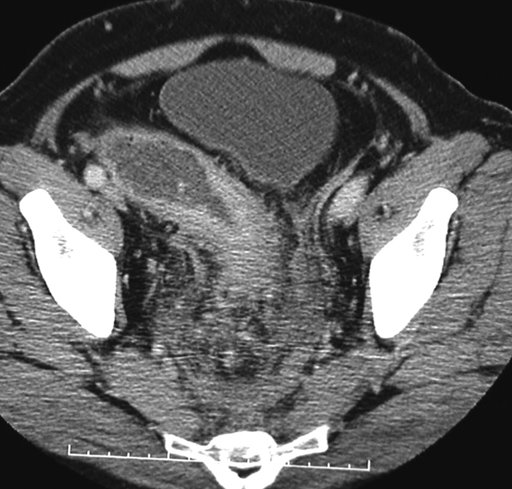

Siêu âm qua ngã trực tràng không đáng sợ như bạn nghĩ!

Việc siêu âm đường tiêu hóa đặc biệt là siêu âm qua ngã trực tràng thường gây bối rối cho mọi người. Tuy nhiên đây chỉ là một thủ thuật y tế đơn giản mà MEDLATEC hôm nay sẽ giới thiệu đến các bạn độc giả qua bài viết lần này.